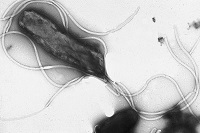

| Helicobacter pylori--Courtesy of Dr. Yutaka Tsutsumi, Fujita Health University School of Medicine |

Helicobacter pylori, or H. pylori, is a bacterium that infects the stomach and causes chronic gastric inflammation, which can lead to ulcers and stomach cancer. H. pylori is found in an estimated 50% of the human population.